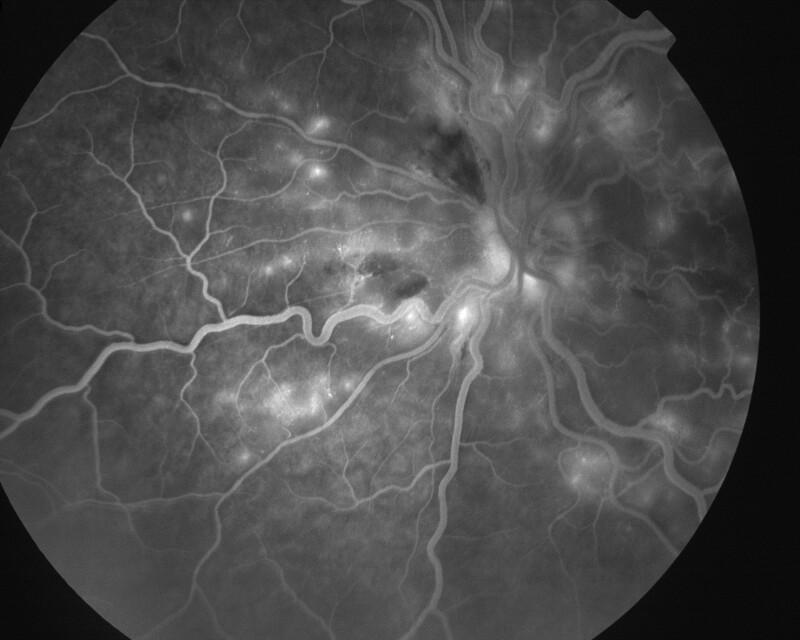

RETINOPATHIE HYPERTENSIVE

IM000019.jpg